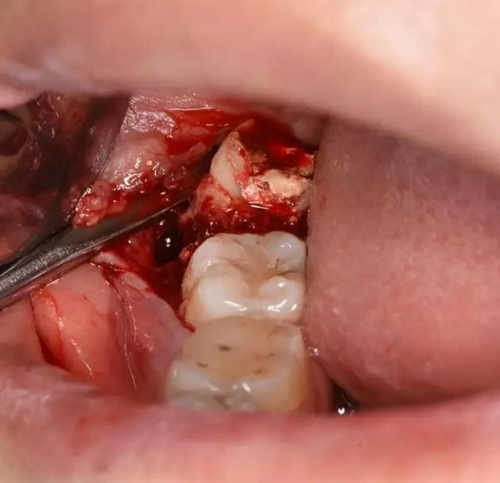

圖1.術(shù)前口內(nèi)觀:48合面齲壞,牙冠萌出1/2,37頰側(cè)牙齦紅腫。

圖6. 剪刀做遠(yuǎn)中小切口、暴露遠(yuǎn)中邊緣嵴

圖7.骨膜剝離器翻開牙齦、暴露48合面

圖8.近中放置牙挺、挺松48